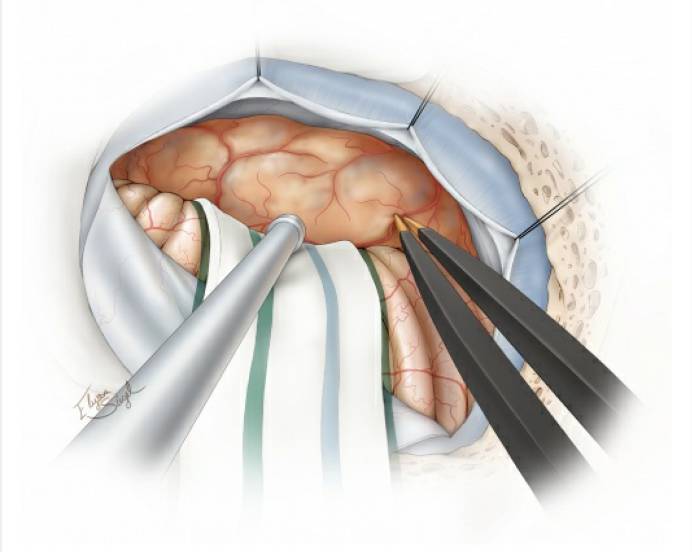

图11. 使用棉片将小脑外侧与肿瘤分离,并标记相应的分离界面。此时分离肿瘤最安全的方法是从内侧向外侧分离(“滚动分离”),这样能较早的发现进出脑干的颅神经根部(上图)。中间的术中图像显示了这个由内向外的分离操作;箭头所指为面神经REZ区。下图提示,肿瘤供血动脉(箭头所示)应沿血管追踪至肿瘤包膜,确认无误后方可离断(“*”号所指为面神经),这一技巧能安全保留过路动脉(包括迷路动脉)。

图12. 清晰显示发自小脑上动脉分支的肿瘤供血动脉,将其分离追踪至肿瘤,然后电凝并离断。将肿瘤从三叉神经根部和桥脑外侧缘进行锐性分离,注意保护好桥脑腹侧表面的软脑膜静脉。此时有必要继续逐步瘤内减压使肿瘤松动,可避免将重要结构置于牵拉损伤的境地。

图13. 最后,仔细检查肿瘤包膜,确保分离完全后,再分块切除肿瘤。有时,三叉神经粘连异常紧密,需非常小心地分离以避免术后出现三叉神经功能损伤。注意,所有脑干表面的软脑膜必须完好无损。最后可放置几块罂粟碱浸润的明胶海绵,以减轻颅神经和脑干上的小血管痉挛。

图14. 关颅前,仔细检查所有重要的神经血管结构,确保其解剖完整性。切除或电凝附近岩骨的硬脑膜以降低肿瘤复发风险,注意该操作不要引起对出骨孔处颅神经的热损伤。此外,受侵犯的岩骨也需磨除。